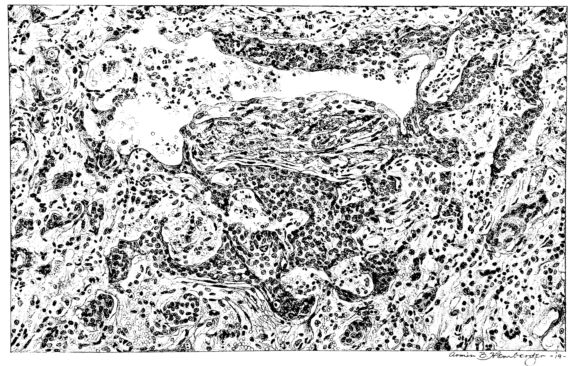

Sections from those areas of the lung where the involvement is more marked may show a histological picture not unlike that described for the aplastic stage, but, in addition, there are groups of lobules where the exudate is typically purulent and pus cells not only form the greater part of the exudate in the lumen, but are prominent in the distended vessels of the alveolar wall (Fig. XXIX). Often these leucocytes are multilobed and frequently their protoplasm is granulated with phagocytized bacteria. The bacteria are also encountered free in the alveolus along with other elements; namely, red blood cells, strands of fibrin, or precipitated albumin (Fig. XXI). The bacteria, however, are not particularly conspicuous, for generally they are either single, in pairs, or in chains; and it is only when they become clumped to form large masses, often larger than any normal tissue cell, that they attract attention. When this appearance is encountered, the alveolar wall is no longer distinct and well preserved. Although the wall may still be made out, it often stains rather homogeneously and much of the finer architecture is lost in the thrombo-necrotizing process that has been instituted (Fig. XVII).

From this intermediary stage the picture of actual abscess with mortification of bronchiolar and alveolar tissue, as well as of the exudate itself, is readily approached (25, 48, 110, 140) (Fig. XXXI). In the necrotic mass that forms the center of such a focus, the most prominent feature is the bacteria. With hematoxylin they stain intensely as black, 26irregular masses, and their prominence is accentuated by the homogeneous staining qualities (with eosin) of the dead tissue, whether lung or exudate (Fig. XXXII). These abscesses may have central cavities which represent a discharge of their contents and may indicate the position of a bronchiole (Fig. XXXI). The necrosis of the alveolar walls, focal in its distribution as previously described, suggests itself as a forerunner of the more extensive necrosis encountered at this stage.

The most extreme form of mortification is seen in the wall of a gangrenous cavity, and several layers can be distinguished there. Beginning with that portion of the lung the least involved, the lesion may be limited to congestion of the alveolar wall with a serofibrinous exudate in the lumen, but this stage passes rather rapidly into another where cellular exudate, chiefly of polymorphonuclear leucocytes, predominates. Moreover, the leucocytes form not only the bulk of the alveolar content, but also distend the vessels and accumulate in the interstitial tissue around blood vessels and lymphatics. Passing toward the center of the gangrenous cavity, the lung rapidly changes in appearance. The blue zone of leucocytic infiltration makes more conspicuous the inner area of necrosis—where nuclei no longer stain and the alveolar wall is a homogeneous pink.

Gradually this phantom architecture, spotted only here and there with disintegrating polymorphonuclear leucocytes, ends in a ragged compressed border of a shaggy pink material which has no identifying qualities (Fig. XXXV). In the inner zone of pink an occasional vessel or, at times, a bronchiole more resistant to the process remains; frequently it is accentuated by the presence of partially destroyed polymorphonuclear leucocytes at its periphery. Probably these cells invade the necrotic areas along the sheath of the bronchus or vessel and not across the dead area. The thrombotic process described in the previous stage (Fig. LII) associated with an acute arteriolitis, may be associated with these gangrenous areas as well as with infarcts (82), but more likely gangrene is preceded by the acute diffuse necrosis of the alveolar wall which occurs in the fulminating cases. Furthermore, this is suggested where a typical grey hepatization is associated with marked thinning, but not actual disappearance, of the alveolar wall. Before concluding the description of this stage of the disease, mention should be made of the granular nodules of fibrin superimposed upon the swollen pleural cells and also of the older pleural exudate, either typically fibrinopurulent or more homogeneous with broken nuclear fragments (Fig. XXXVIII).